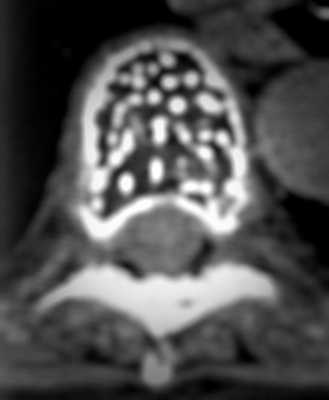

На изображении представлен поперечный срез через позвонок. В теле позвонка - типичная гемангиома (H). Цифрой 1 отмечены утолщенные и разреженные трабекулы губчатого вещества, цифрой 2 - периваскулярные пространства, сосудистые лакуны. При компьютерной томографии они имеют низкую плотность, приближающуюся к плотности жира (гемангиолипома).

Типичная гемангиома в грудном позвонке. На аксиальном срезе - справа - отчетливо виден характерный «точечный» «рисунок», обусловленный утолщением трабекул и большим количеством периваскулярного жира.